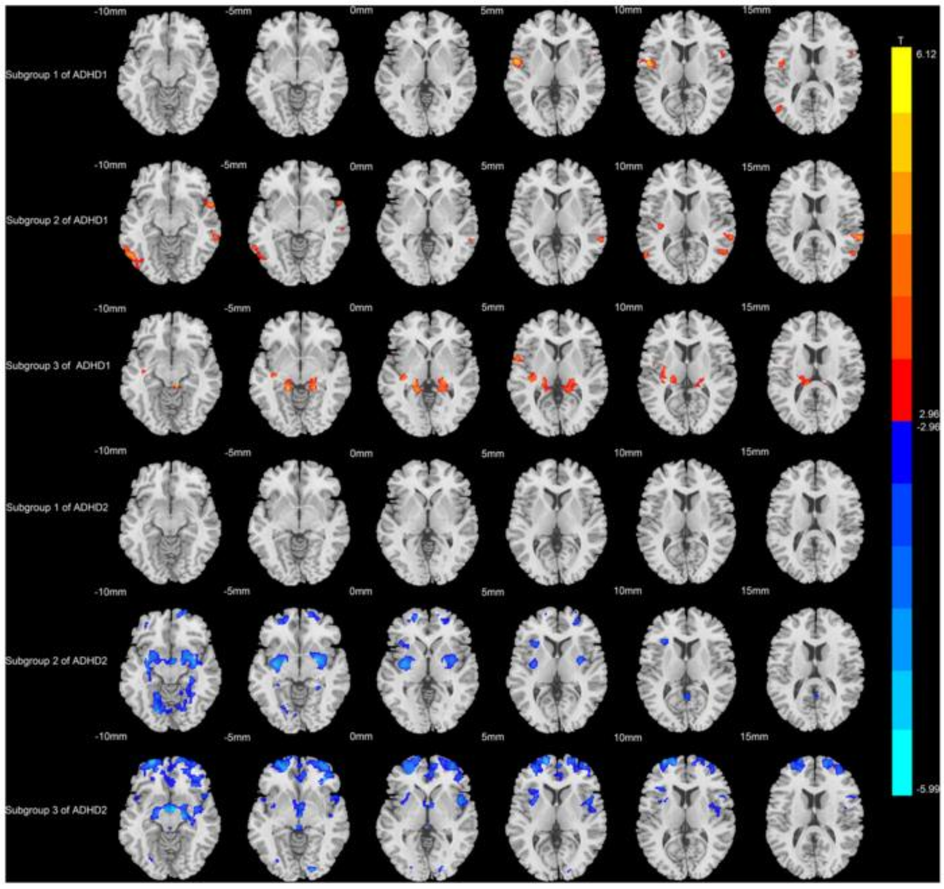

На лабораторных снимках у детей и взрослых с СДВГ видны структурные и функциональные отличия в базальных ганглиях и префронтальной коре. Эти области связаны с переработкой вознаграждения и исполнительными функциями – умением планировать, переключаться и управлять вниманием. Метанализы нейроизображений показывают, что именно аномалии в путях между таламусом, стриатумом и корой приводят к нарушению самоконтроля. Одна из современных моделей – «двойной путь» – выделяет два независимых компонента: дефицит реакции на торможение и отвращение к задержке вознаграждения (delay aversion). Последнее заставляет человека предпочитать небольшую награду сейчас вместо большой в будущем. Такой мозг буквально не видит смысла напрягаться без мгновенного вознаграждения.

После примерно 9 часов гиперфокуса наступает странное состояние: словно в голове шум, и хочется бросить всё и лечь “плевать в потолок”. Это перегруз исполнительных функций. Отсутствие гибкости сетей, регулирующих внимание, приводит к тому, что мозг либо полностью включён, либо отключается. Причём это выключение может случиться внезапно, даже если задача ещё не доведена до конца. Объяснить это сложнее, но изображения мозга показывают, что у людей с СДВГ снижена эффективная связь между сетями исполнительного контроля и дефолт‑системой, что приводит к чувству «мозгового шума» и необходимости перейти к другому занятию.

Несмотря на стереотипы, СДВГ – один из самых изучаемых нейроразвитий. Генетические исследования показывают, что это состояние наследуется: доля наследуемости, по разным оценкам, составляет 70–80 %, а недавние анализы полного экзома связывают повышенный риск с редкими вариантами генов, связанных с функционированием синапсов и дофаминовой системы. Нейроизобразительные исследования свидетельствуют о том, что у детей с СДВГ кортикальные области и белое вещество созревают медленнее, особенно в префронтальной коре, ответственной за планирование и самоконтроль. При этом связь между центрами вознаграждения и контролем нарушена, что приводит к зависимости от мгновенных наград и трудности с отложенной выгодой.